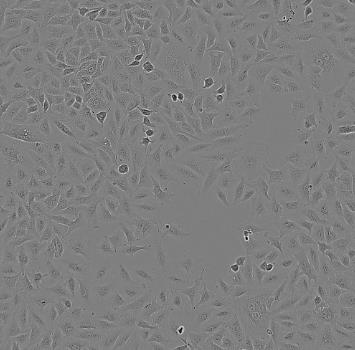

CAL-62人甲状腺癌贴壁细胞系是1988年从一名患有甲状腺间变性癌的70岁女性的甲状腺(右叶)建立;被描述为在异种移植裸鼠中致瘤。